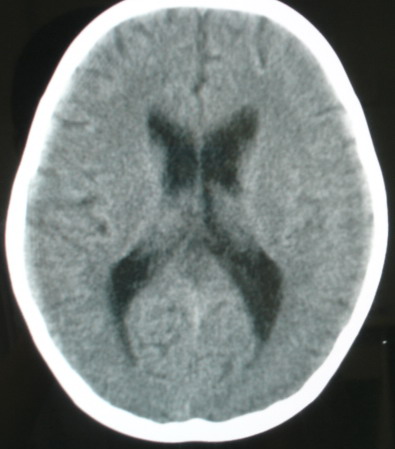

m/8y,右侧眼睑下垂数天,头昏,无呕吐、无外伤史。无搏动性突眼。病人明天来增强。

考虑颈内动脉海绵窦段动脉瘤,建议mri检查。

考虑 颈内动脉海绵窦段动脉瘤.

考虑海绵窦血管瘤,做mri效果比较好。